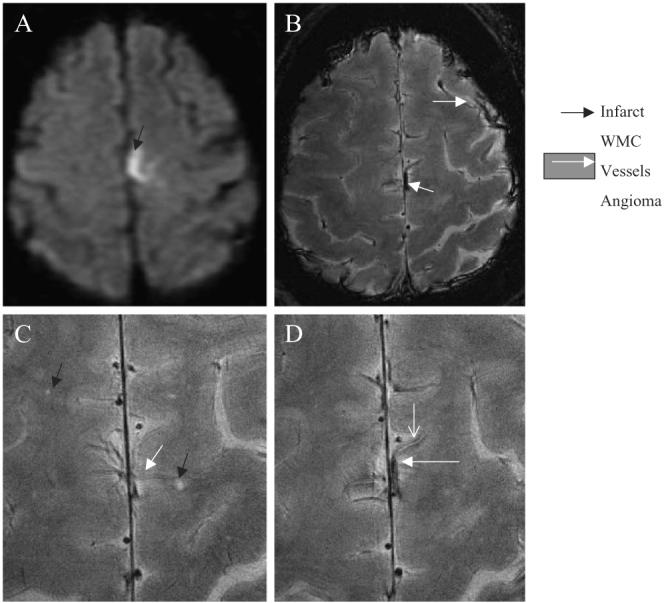

The subject suffered from the second hemorrhagic cortical stroke 2 years later and was imaged with 1.5-T MRI only. Fig. 3 shows an axial 1.5-T FSE T2-weighted image of the left hemispheric infarct (A). We have reviewed 8-T GE images that were obtained 2 years prior to this event. High-resolution 8-T GE slices through the cortex (B–D) revealed a cortical angioma in the location of the second hemorrhagic infarct. The angioma-feeding vessel appeared hyperintense with a low-signal intensity border. Punctuate white matter lesions (3−4) were seen scattered within this area. A distended superficial cortical vein was clearly visible in the left temporal region.

Fig. 3.

Axial 1.5-T FLAIR image of the second subacute left hemorrhagic hemispheric infarct (A) (black arrow). High-resolution 8-T GE images (B-D) that were obtained 2 years prior to acute event show an angioma in the same location (white arrow), prominent superficial and scattered punctuate white matter changes (black arrow) (C). The angioma feeding vessel shows a high-signal intensity surrounded by a low-signal intensity rim, suggestive of iron deposits. The 8-T GE: BW=69.4 kHz, FOV=20×20 cm2, slice thickness=2.3 mm, TR=602.7 ms, TE=10.0 ms, matrix=1024×1024, N=18. The 1.5-T FLAIR: slice thickness=5 mm, TR=10000 ms, TE=140 ms, inversion time, TI=2200, matrix=192×256, number of slices=16.

Fig. 4 shows comparisons of 1.5-T FLAIR and T2-weighted FSE and 8-T GE and RARE images that were acquired from a 63-year-old woman 2 months after a transient episode of right-face and a right-upper extremity weakness (Table 1, case 2). The 1.5-T FLAIR (A) and the T2-weighted FSE (C) images at the level of ventricles were unremarkable, except for few small white matter changes in the corona radiata and the pons. Left temporal hemorrhagic infarction was seen on the 8-T GE (B) and the RARE (D) slices as a characteristic high-signal intensity area with a low-intensity border. On the 8-T RARE images, the infarction appeared to extend into the white matter. An incidental venous angioma (E, F) in the right periventricular white matter was seen on the 8-T GE images, which was not apparent on 1.5-T images.

Fig. 4.

The 1.5-T FLAIR (A) and T2-weighted FSE (C) images at the level of the ventricles were unremarkable. The 8-T GE image (B) shows the left temporal hemorrhagic infarct as a high-signal intensity area (black arrow) with a low-signal intensity boundaries. The infarction appeared larger on the 8-T RARE image (D). The 8-T GE images (E, F) show an incidental angioma (white arrow) in the right periventricular white matter that was not apparent on the 1.5-T images. The 8-T GE: BW=50 kHz, FOV=20×20 cm2, slice thickness=5 mm, TR=750 ms, TE=10 ms, matrix=512×512. The 8-T RARE: BW=50 kHz, FOV=20×20, slice thickness=5 mm, TR=750 ms, TE=10 ms, matrix=512×512. The 1.5-T FLAIR: TR=4000 ms, TE=148.5 ms. The 1.5-T T2-weighted FSE: TR=5417 ms, TE=104 ms.

The relationship of the lacunar infarctions and penetrating small vessels is demonstrated on the high-resolution 8-T GE and RARE images (Fig. 5 A, B) obtained from a 45-year-old woman with a history of recurrent TIAs (Table 1, case 3). Normal medullary veins are seen as dark lines that run in parallel to the left temporal lacunar infarction. Fig. 5 C shows the second lacunar infarction at the termination of a small penetrating vessel. This vessel shows an inhomogeneous high- and low-signal intensity pattern. The proximal segment appears as a dark line of the signal “void,” typical for normal blood flow that is replaced by high-signal intensity in a distal segment. The vessel terminates in a high-signal intensity area, suggestive of a lacunar infarction. Fig. 5 D is an 8-T RARE image that shows both infarcts, the vessel with mixed signal intensity and punctuate white matter changes. The 1.5-T MRI was not repeated. The pattern of vessels with inhomogeneous signal intensity was distinct from characteristic “signal-void” vessels that has been demonstrated in healthy volunteers.

Fig. 5.

High-resolution axial 8-T GE slices show the left temporal lacunar infarction (A–C) as high-signal intensity area and normal-appearing penetrating vessels as linear signal voids. Panel C shows the cortical vessel with inhomogeneous signal intensity (white arrow) (C). This vessel terminates in a high-signal intensity area, suggestive of the second lacunar infarction (black arrow). The normal pattern of signal void is replaced in a distal vessel segment by high-signal intensity. The 8-T RARE image (D) shows both infarctions (black arrows), cortical vessel with inhomogeneous signal (white arrow) and additional punctuate white matter changes (black diamond). Gradient echo and RARE images were acquired with the following parameters: GE: BW=69.4 kHz, FOV=20×20 cm2, slice thickness 2.3 mm, TR=600 ms, TE=10 ms, matrix 1024×1024; RARE: BW=69.4 kHz, FOV=20×20 cm2, slice thickness=2 mm, TR=3000 ms, TE=22 ms, matrix=512×512, RARE factor 4.